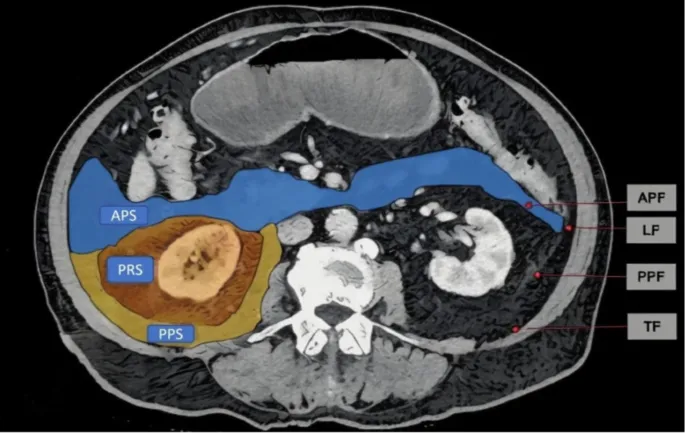

- Retroperitoneum: Space posterior to the parietal peritoneum.

- Anterior Pararenal Space: Contains pancreas, duodenum (2nd-4th parts), ascending & descending colon.

- Perirenal Space: Encases kidneys, adrenal glands, ureters, aorta, IVC, and perirenal fat.

- Posterior Pararenal Space: Contains fat and nerves.

- Key sign: Anterior displacement of bowel/pancreas. Spaces: Anterior pararenal, perirenal, posterior pararenal.

- Retroperitoneal spaces (anterior pararenal, perirenal, posterior pararenal) are key for localization.